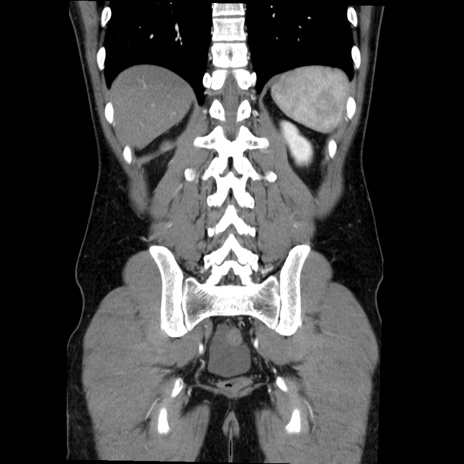

症例36(冠状断像)

【症例】20歳代 男性

【主訴】心窩部痛

【現病歴】今朝より上腹部痛あり。一旦軽快していたが再度出現したため救急要請。昨日夕に白身の魚を含む刺身を食べた。

【身体所見】BP 136/89mmHg、HR 74/min、BT 37.0℃、腹部:膨満、軟、心窩部に圧痛あり。反跳痛なし、筋性防御なし、腸雑音やや亢進あり。

【データ】WBC 17700、CRP 0.48